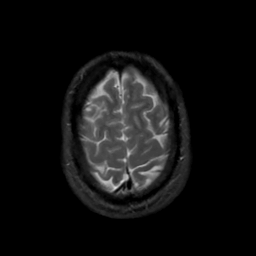

MR Study #6, March 17, 1991 -- Slice #43

[Home][Help][Clinical][Tour 1][Tour 2] Slice 43